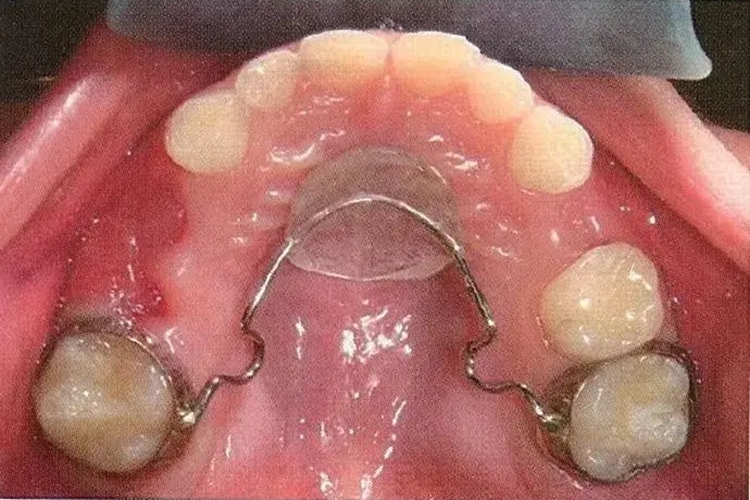

腭弓式间隙保持器

腭弓也称南斯弓。将舌弓的两端固定在第二乳磨牙或第一恒磨牙上,以保持上颌牙弓周长的装置。